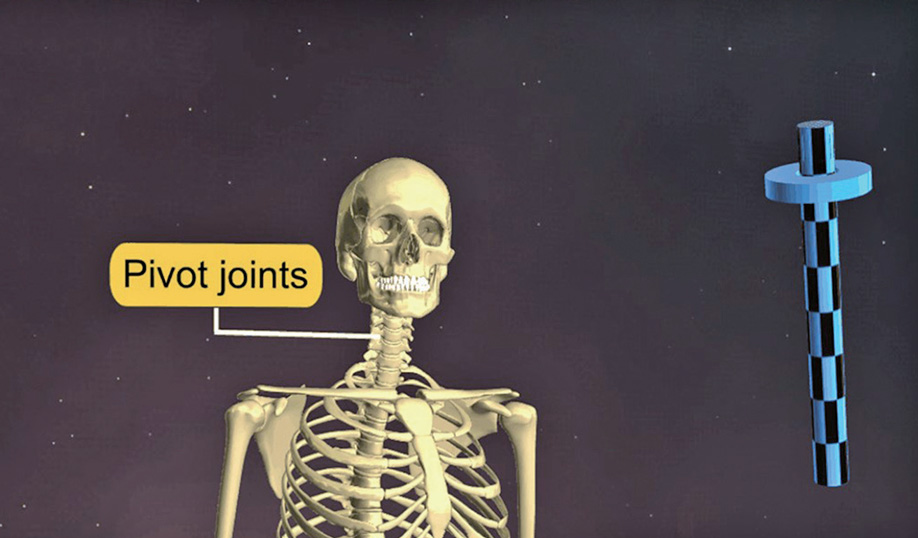

이와 같이 잘 움직이지 않는 부동관절에 비해 가동관절은 실제 움직이는 관절이기 때문에 참관절(true joint)이라고 부릅니다. 이 가동관절은 움직임의 종류에 따라서 여러 가지로 나눕니다.

- 가동관절③ 중쇠관절